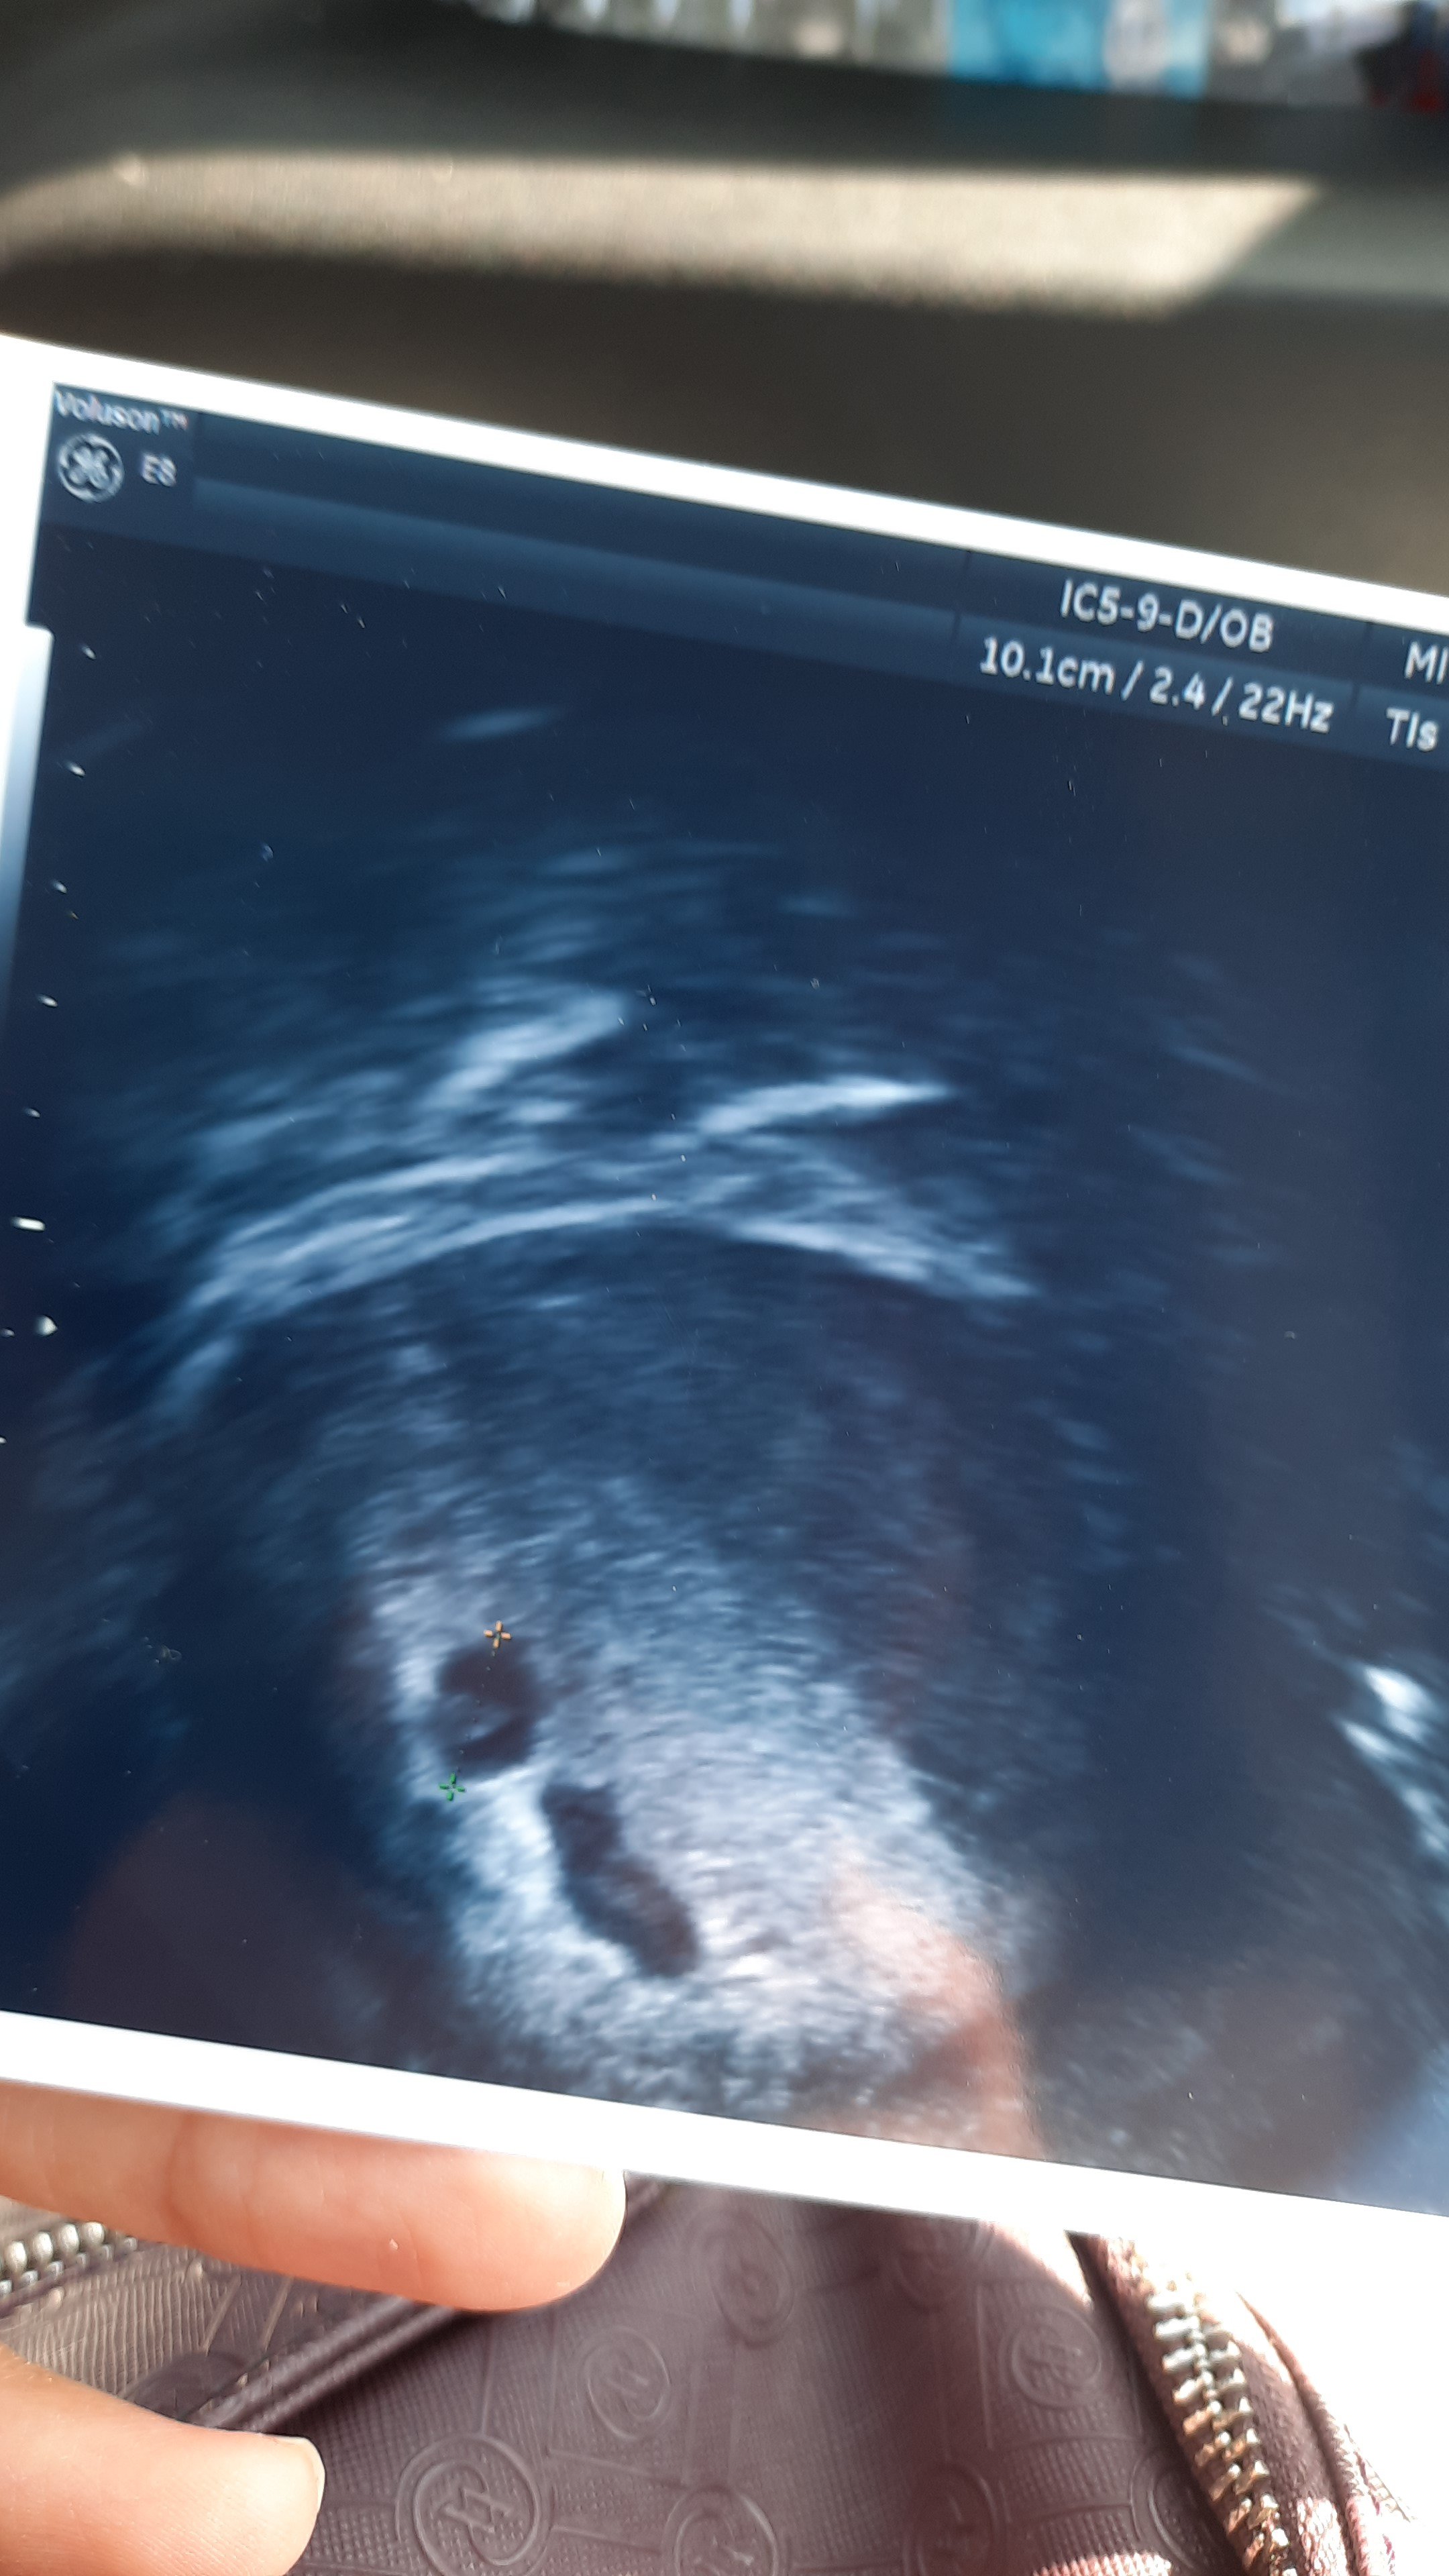

Canım attım bakarsın ilk attığım 1 inci keseyi görmeye gittiğimde hersey güzeldi ama kesenin altında kese gibi bisey vardı ondada kan vardı o bozabilir sürekli dinlen yat dedi kanama tehliken var dedi ama 2inci si 1 inci olan gibi kalmış buyur mu umutlaniyorum ama okuduklarımi görünce umudum da kalmıyor rabbim bilir dedim

• 20220416_181600.jpg

20220416_181600.jpg

1,018.9 KB · Görüntüleme: 173